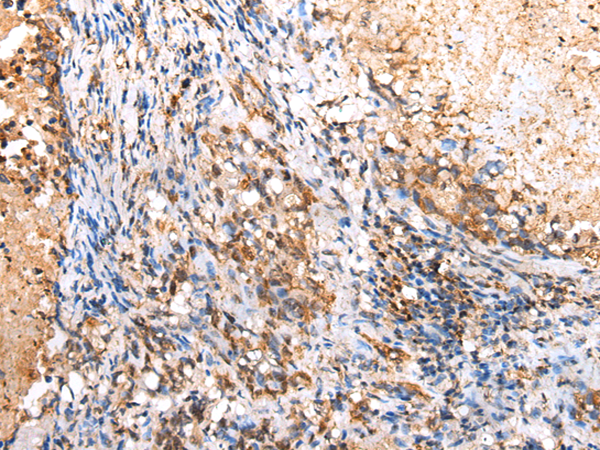

分类: 科研抗体货号: P02100别名:应用: WB,IHC反应种属: Human, Mouse

分类: 科研抗体货号: P02020别名: Ipi3; R32184_1应用: WB,IHC反应种属: Human, Mouse

分类: 科研抗体货号: P01920别名: HAT应用: WB,IHC反应种属: Human, Rat

分类: 科研抗体货号: P02094别名: EMC5; TMEM32应用: WB,IHC反应种属: Human, Mouse, Rat

分类: 科研抗体货号: P01915别名: CAPH2; MT-SP2; TMPRSS3应用: WB,IHC反应种属: Human, Mouse

分类: 科研抗体货号: P02005别名:应用: WB,IHC反应种属: Human, Mouse, Rat

分类: 科研抗体货号: P02092别名: NAAGS; FAM80B; NAAGS-I应用: IHC反应种属: Human, Mouse

分类: 科研抗体货号: P02085别名: ECO; ICK; MRK; LCK2; EJM10应用: IHC反应种属: Human, Mouse, Rat

分类: 科研抗体货号: P02002别名:应用: WB,IHC反应种属: Human, Mouse